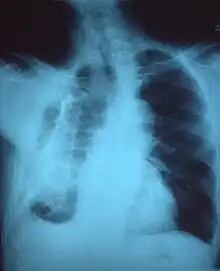

Chest x-ray showing fibrous opacity on one side

Fibrothorax on chest x-ray